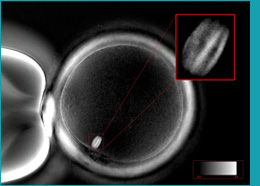

In a breakthrough in optics and computational technology, this chromosome spindle can now be visualized in real time, while actually injecting the eggs. This would prevent egg damage, increase fertilization rates, increase embryo formation rates and improve embryo quality. A machine called Poloscope, makes use of optical deviation of light waves as it passes through the egg placed under a microscope. This deviation is then fed into a computer. Based on the computer analysis, the spindle is located. We can also have an accurate picture of the maturity of the egg as well as quality, by assessing the clear and high resolution images of the meiotic spindle. Any abnormality of spindle has high risk for developing into embryos with chromosomal abnormalities. This may result in failed fertilization, poor embryo development, failed implantation or spontaneous abortion. So, this machine can be used as a screening method to avoid implanting an embryo with genetic risk. The machine can thus help to improve fertilization rates and pregnancy outcomes.

Chromosome spindle of egg seen

with the aid of Oosight